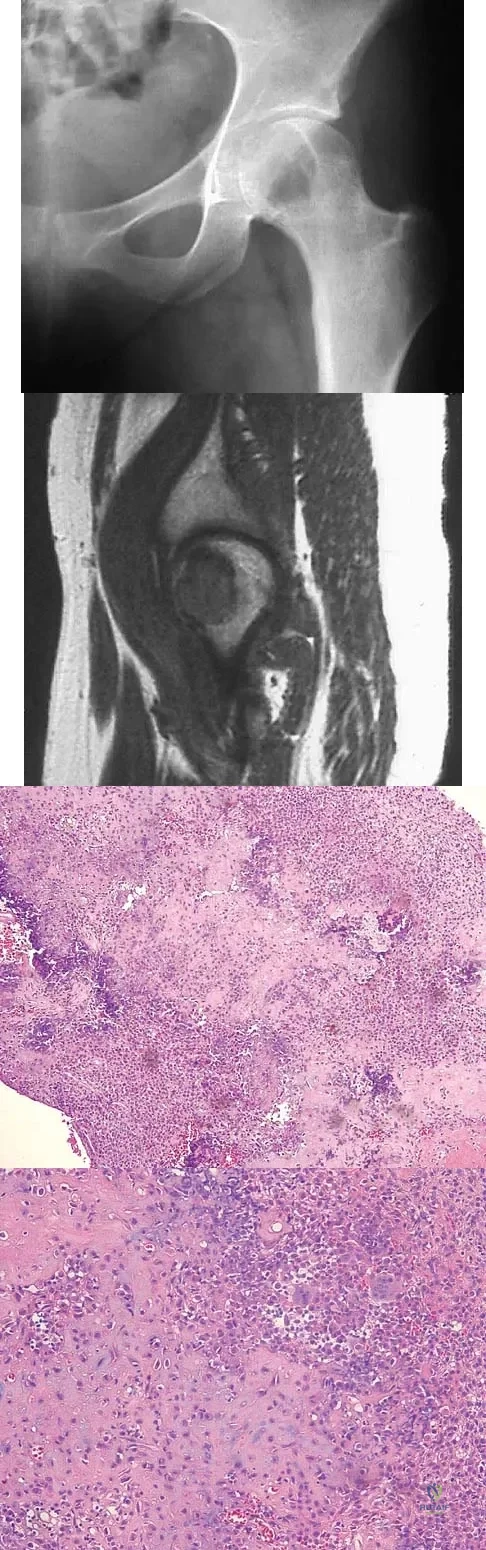

Question 61High Yield

A 16-year-old girl has had pain in the left groin for the past 4 months. She notes that the pain is worse at night; however, she denies any history of trauma and has no constitutional symptoms. There is no history of steroid or alcohol use. Examination reveals pain in the left groin with rotation of the hip. There is no associated soft-tissue mass. A radiograph and MRI scan are shown in Figures 32a and 32b, and biopsy specimens are shown in Figures 32c and 32d. What is the most likely diagnosis?

Explanation